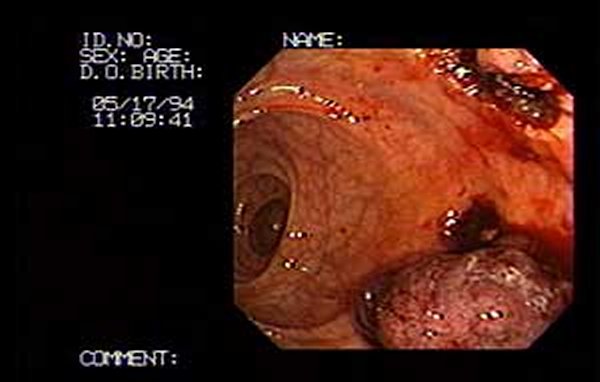

Ulceración post polipectomía endoscópica de tumor precanceroso de gran tamaño.

La ulceración en fase de cicatrización ocho días después de la resección transendoscópica. El tejido granula en forma gradual, la fibrina está organizada en un promedio de dos semanas. Cicatriza completamente. El paciente se beneficia al no tener una cirugía abierta. Y lo más importante es salvarse de un cáncer. Este tumor precanceroso no se formó en un día, estos tipos de tumores pasan años en crecer y la única forma de detectarlos es por medio de los exámenes que practicamos a diario. No se deje ser sorprendido por un cáncer. Revise su cuerpo el cáncer en sus inicios (varios años no da síntomas)